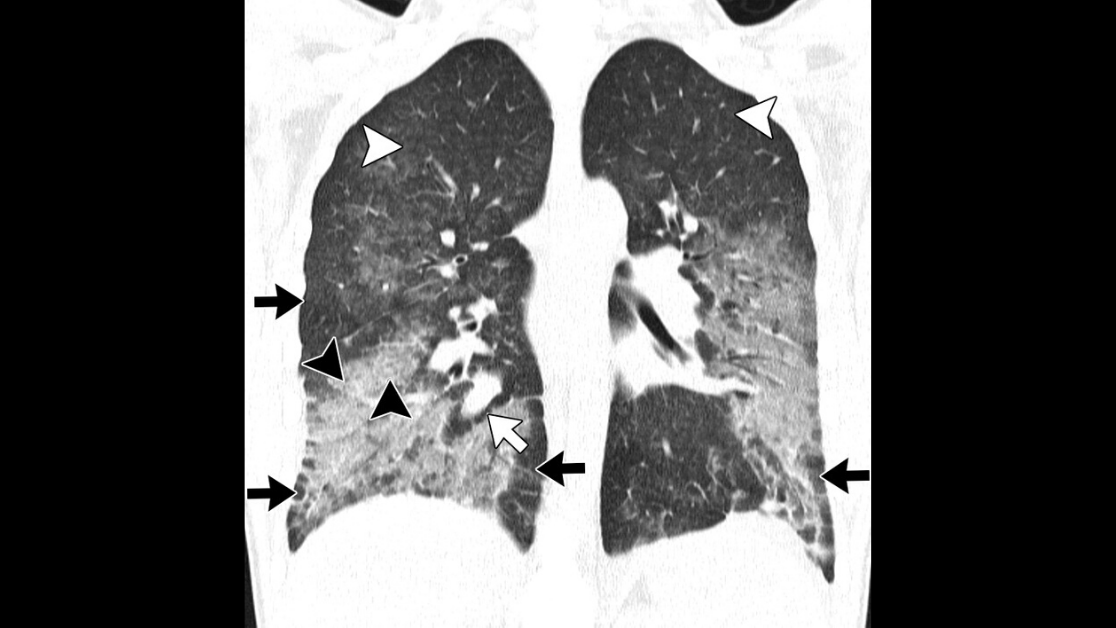

What are the CT characteristics of T790M mutation--positive non--small cell lung cancer after tyrosine kinase inhibitor therapy failure? Find out in this article by Koo et al.pic.twitter.com/CEw1GK4Ku0